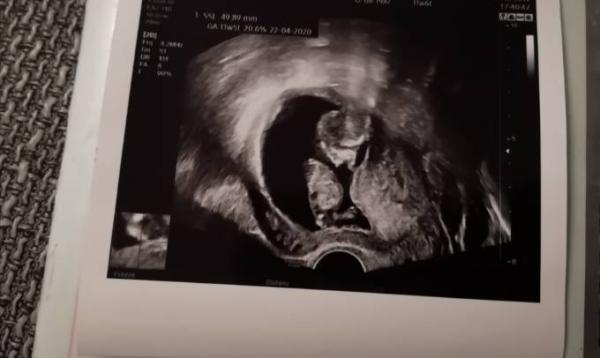

Ich hatte gestern Abend einen Termin. Es ist alles super und unser Mäuschen hat fleißig gewunken Auch an Größe hat Krümel aufgeholt und ist bei 5 cm Der Et bleibt auf dem 28.04,der FA meint wir datieren nicht nochmal um. Ich bin erleichtert, daß alles gut ist. Die langen Wartezeiten können einen echt irre machen. Heute rutsche ich in die 12te woche

Bild zu Fa Termin - Forum für April - Mamis